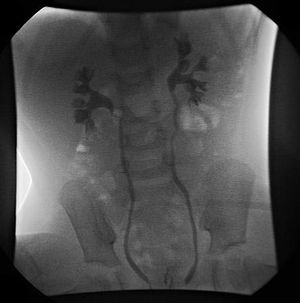

4. 1. 배뇨성 방광 요도 조영술 (Voiding Cystourethrogram, VCUG)

배뇨성 방광 요도 조영술(VCUG)은 방광요관역류의 등급 분류 및 초기 검사에 선호되는 방법이다. 요로 감염이 있는 소아의 경우, 해부학적 원인을 배제하기 위해 VCUG와 복부 초음파 검사를 수행해야 한다.확정 진단은 배뇨 시 엑스레이를 통해 조영제의 역류 여부를 확인하는 배뇨성 방광 요도 조영술로 실시한다.[14][15] 늑골 척추각(CAV) 타진도 신우신염을 나타내므로 유효하다.[16]